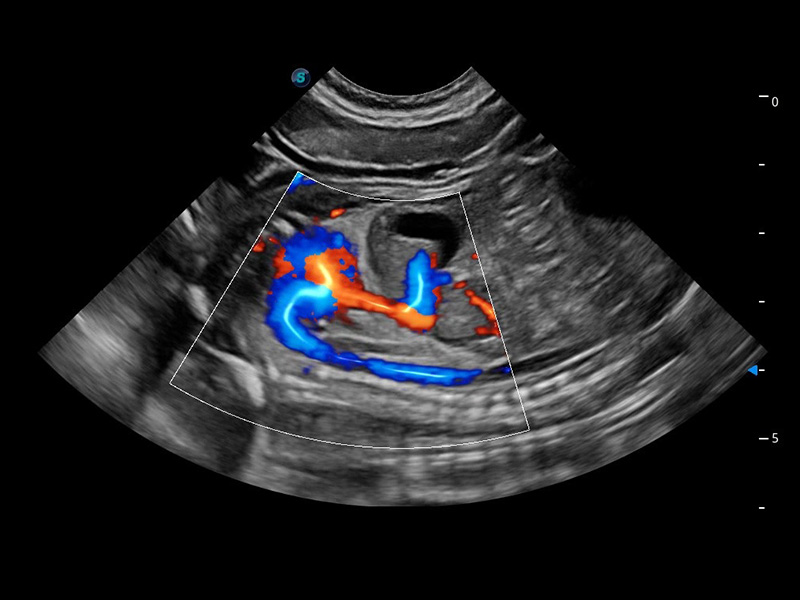

ProPet 60 作为一款高端台式动物超声设备,为动物医生的日常诊断提供了一系列贴合动物临床需求、解决临床实际问题的高级成像功能。凭借全系列高清探头,满足医生对腹部、心脏、生殖、浅表、肌骨等成像的所有需求,切实帮助您提升检查效率,提高诊断信心。

兽用彩色多普勒超声诊断系统

动物是人类最亲密的朋友和最值得信赖的伙伴。狗万官方网站也一直致力于探索动物专用的超声影像解决方案。 全新推出的ProPet系列,是狗万官方网站在动物超声影像智能化、专业化、精准化的一次跨越式革新。动物不能用言语来表述自己的不适,通过超声影像,ProPet系列搭建了动物医生与不同物种沟通的“桥梁”,为动物医生注入了“治愈之力”。